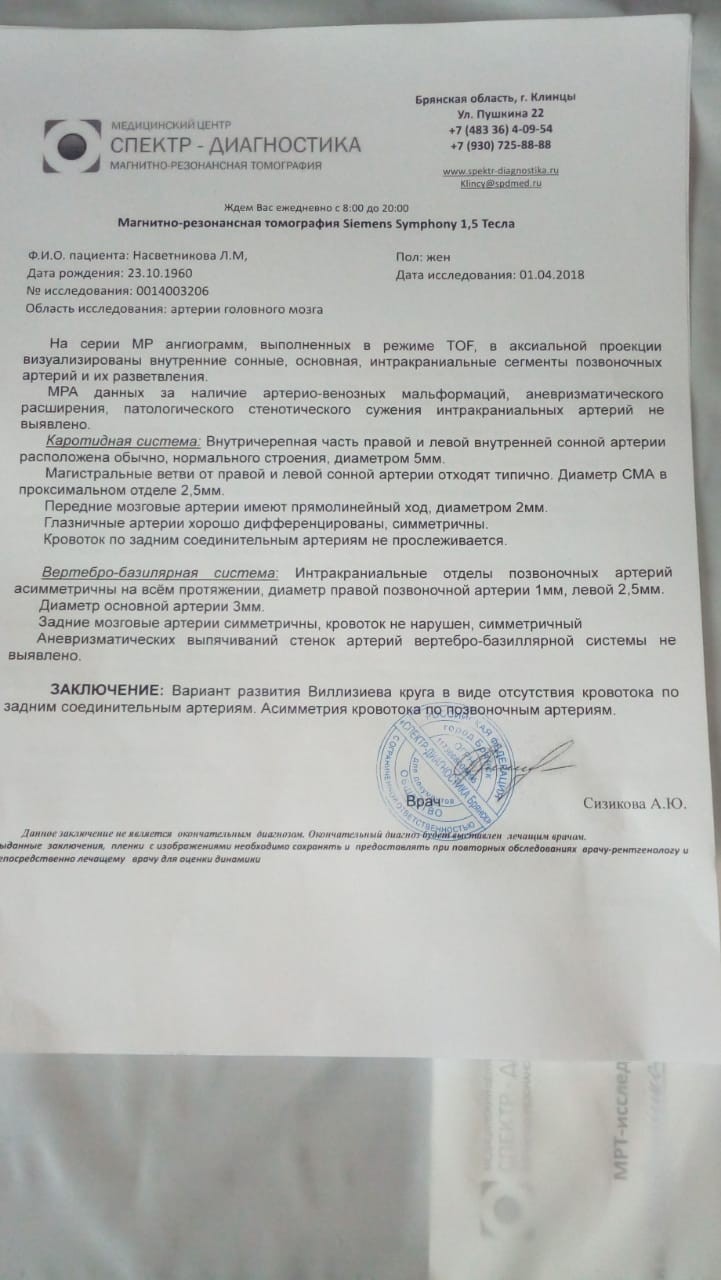

МРТ головного мозга: Расшифровка снимков и Интерпретация

Раздел: Визуальные уроки